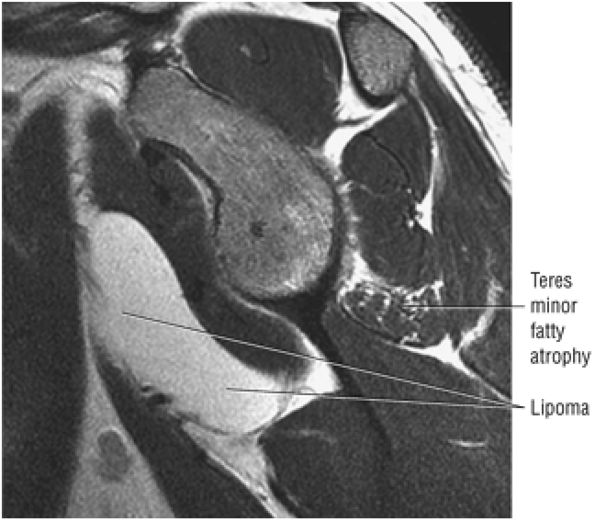

FIGURE 8.16 Teres Minor ● The teres minor functions with the infraspinatus to externally rotate and extend the humerus. The teres minor is active with the shoulder in 90° of elevation.